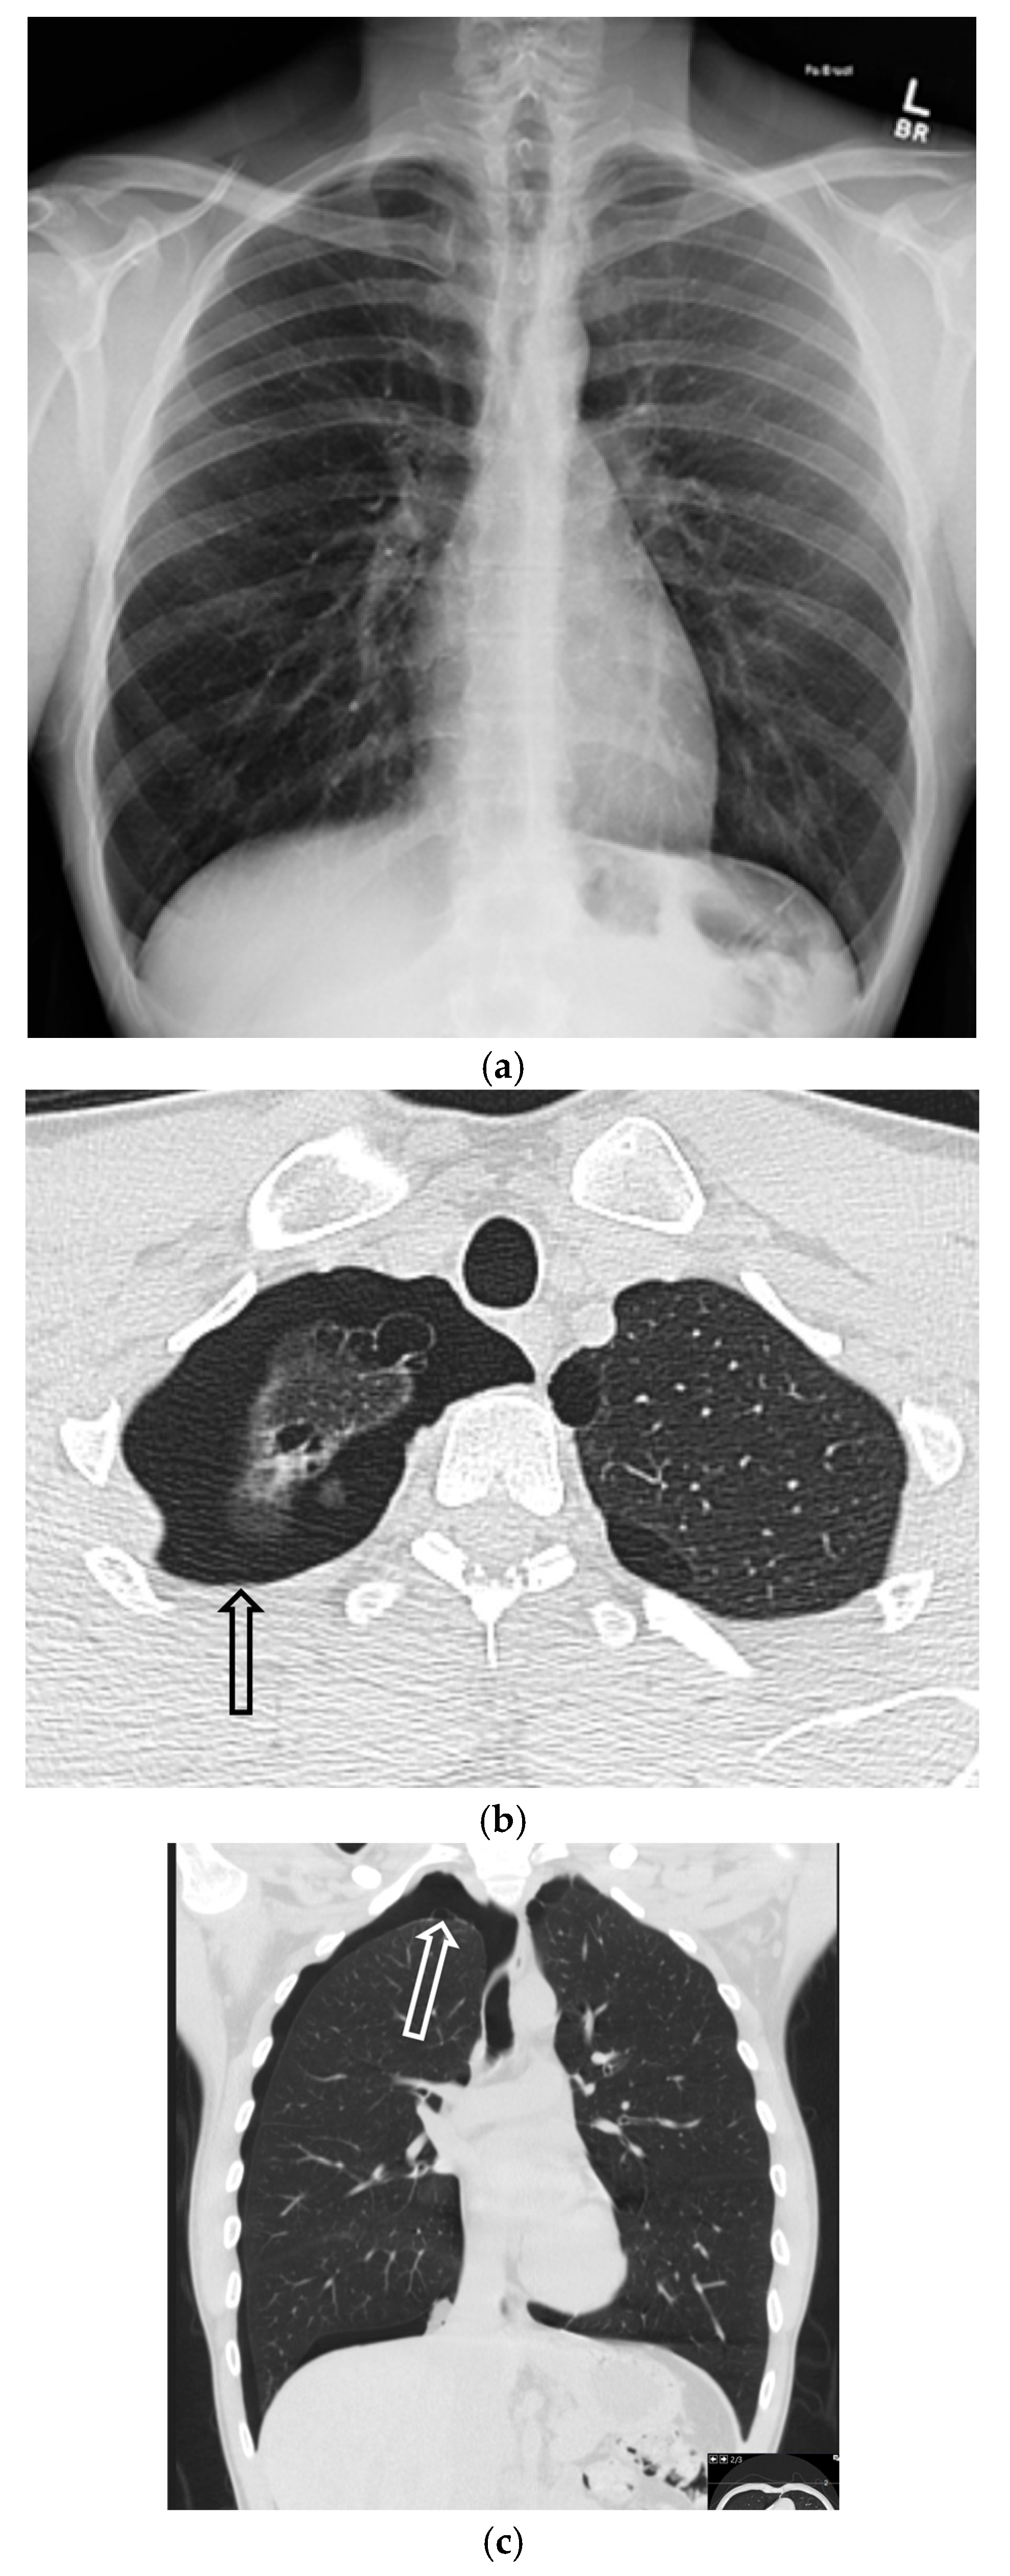

5.2.1. Chronic Obstructive Pulmonary Disease (COPD)

5.2.2. Cystic Fibrosis (CF)